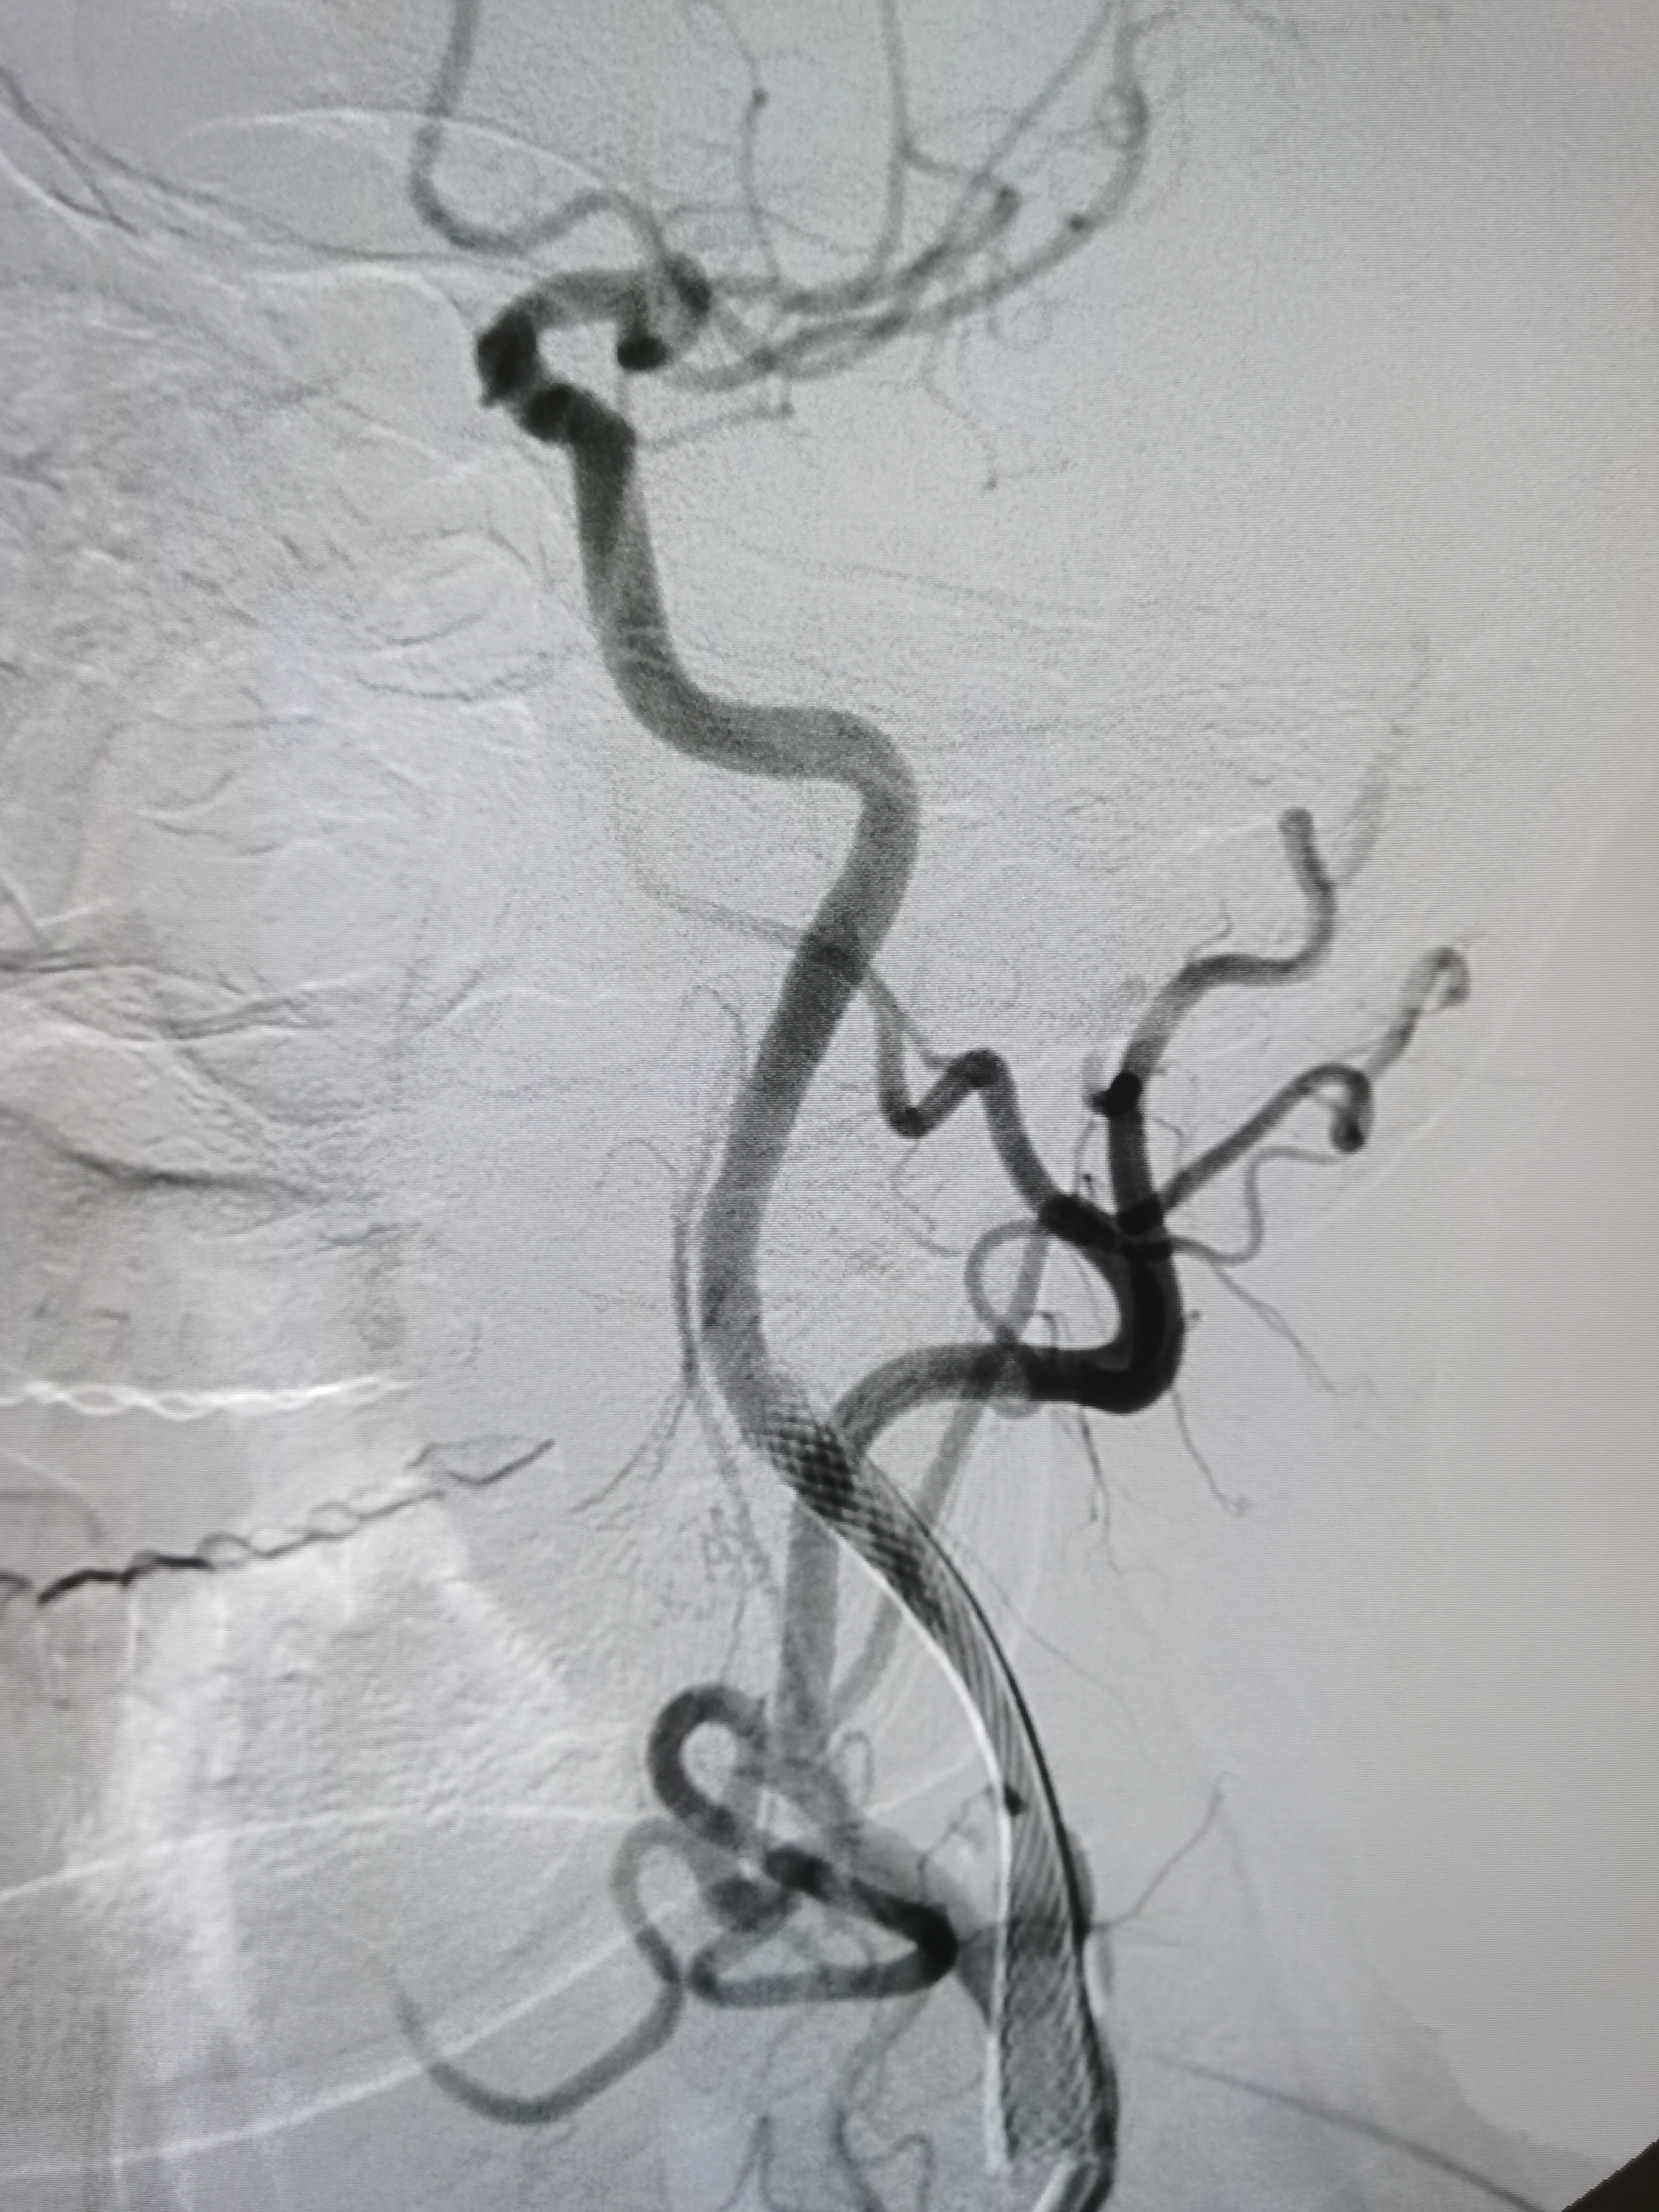

3型主动脉弓

右颈内动脉颅外段正常

右侧胚胎型大脑后动脉。

颅内段显影良好。

左侧颈内动脉起始部次全闭塞,局部斑块不稳定。

术前术后对比